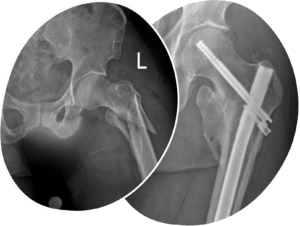

Fractures

Prof Kauta has many years of experience fixing broken bones and replacing broken joints. Where your broken bone involves the hip or the shoulder joint, and you are at an appropriate age for a joint replacement surgery, this option may be best suited for certain fracture patterns.

Prof Kauta will take you through all the options available for the management of your broken bones and you will feel empowered to make the right decision for you.